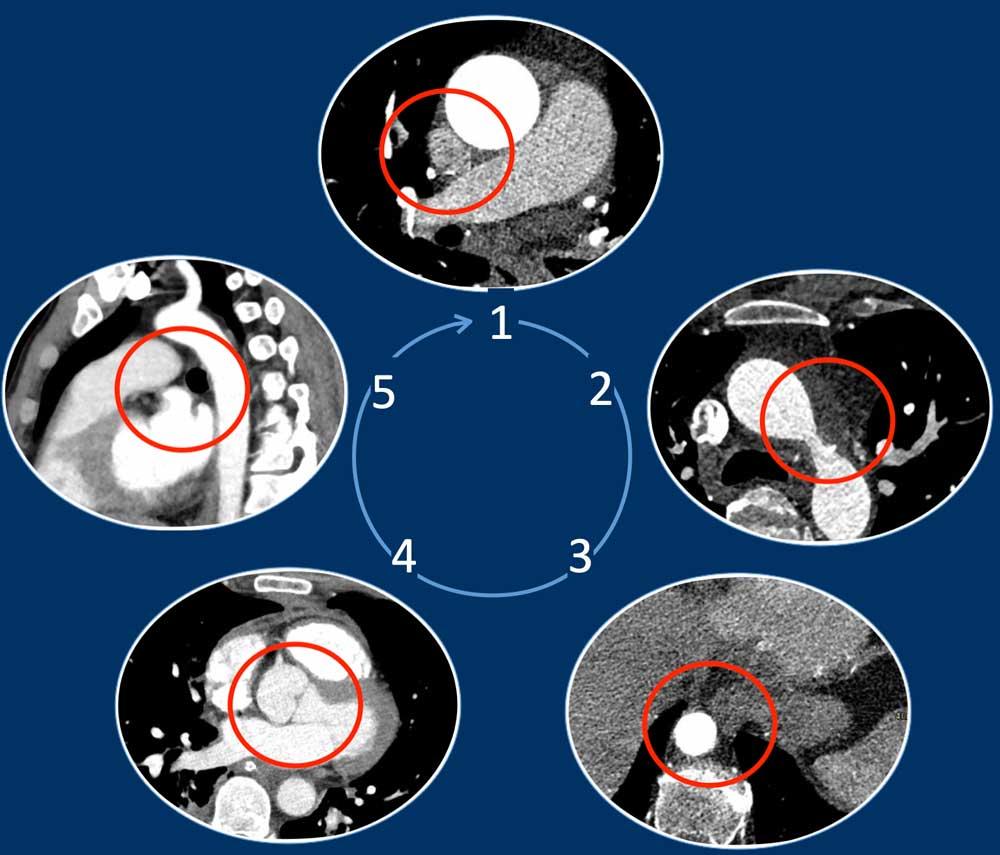

Phương pháp Năm Góc

Phát hiện các bất thường mạch máu trên phim CT ngực không chụp tim có thể là một thách thức, đặc biệt khi chúng không được nghi ngờ trước và do đó không phải là trọng tâm chính của cuộc khảo sát.

Chỉ cần kiểm tra năm góc, có thể phát hiện được phần lớn các biến thể mạch máu:

- Giao điểm giữa tĩnh mạch phổi trên phải và tĩnh mạch chủ trên (mặt cắt ngang)

Chẩn đoán phân biệt: Bất thường hồi lưu tĩnh mạch phổi bán phần (PAPVR) bên phải. - Phía bên ngoài cung động mạch chủ (mặt cắt ngang)

Chẩn đoán phân biệt: Tĩnh mạch chủ bên trái, tĩnh mạch hồng y nhĩ trái, PAPVR bên trái, tĩnh mạch liên sườn trên bên trái. - Động mạch chủ xuống ở mức cơ hoành (mặt cắt ngang)

Chẩn đoán phân biệt: Cấp máu động mạch hệ thống cho phổi, tiếp nối tĩnh mạch đơn thay thế tĩnh mạch chủ dưới, tĩnh mạch Scimitar. - Mức gốc động mạch chủ (mặt cắt ngang)

Chẩn đoán phân biệt: Bất thường nguyên ủy động mạch vành. - Cửa sổ phế động mạch (mặt cắt đứng dọc)

Chẩn đoán phân biệt: Còn ống động mạch, túi thừa động mạch chủ, động mạch dưới đòn phải bất thường.

Bằng cách kiểm tra năm vị trí then chốt này, có thể phát hiện được phần lớn các biến thể mạch máu, đặc biệt hữu ích trong việc phát hiện các bất thường tĩnh mạch phổi (in đậm):

- Giao điểm giữa tĩnh mạch phổi trên phải và tĩnh mạch chủ trên (mặt phẳng axial)

Chẩn đoán phân biệt: Bất thường dẫn lưu tĩnh mạch phổi một phần (PAPVR) bên phải. - Phía bên ngoài cung động mạch chủ (mặt phẳng axial)

Chẩn đoán phân biệt: tĩnh mạch chủ bên trái, tĩnh mạch hồng y levo-nhĩ, PAPVR bên trái, tĩnh mạch liên sườn trên bên trái. - Động mạch chủ xuống tại mức cơ hoành (mặt phẳng axial)

Chẩn đoán phân biệt: cấp máu động mạch hệ thống cho phổi, tĩnh mạch azygos thay thế tĩnh mạch chủ dưới, Tĩnh mạch Scimitar. - Cửa sổ phế động mạch-chủ (mặt phẳng sagittal)

Chẩn đoán phân biệt: còn ống động mạch, túi thừa động mạch chủ, động mạch dưới đòn phải bất thường. - Mức gốc động mạch chủ (mặt phẳng axial)

Chẩn đoán phân biệt: bất thường nguyên ủy động mạch vành.